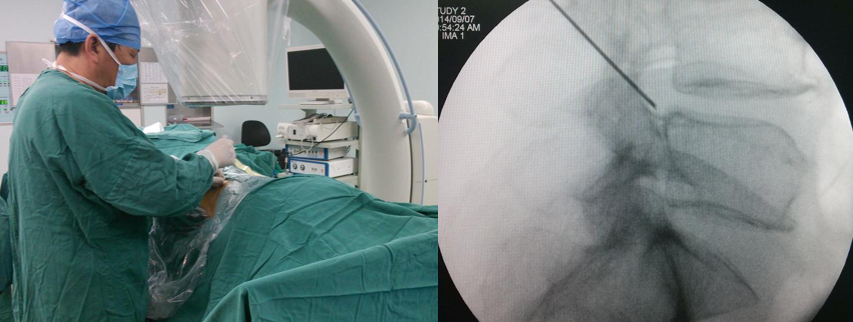

体表定位(用克式针标记进针路线)

椎间盘突出在L2-L3和L3-L4水平,选择在旁开中线10 cm进入。椎间盘突出在L4-L5和L5-S1水平,选择在旁开中线12-14 cm进入。实际的旁开距离还需要依病人的身体大小和肥胖程度作适当调整。肥胖、椎间孔狭小、小关节面假性关节病的病人旁开的距离要大一些。对向下掉的髓核,进入点要偏向头侧和外侧。

体表定位(C型臂下影像)

皮肤消毒

铺无菌治疗巾

穿手术衣和带无菌手套

无菌贴

局部麻醉

放置导丝(扩张软组织)用锋利的小手术刀在进针点皮肤切开一个大约8 mm的切口。沿着导丝向小关节方向插入导杆。在导杆外沿着导杆逐级放套管向外扩张软组织。